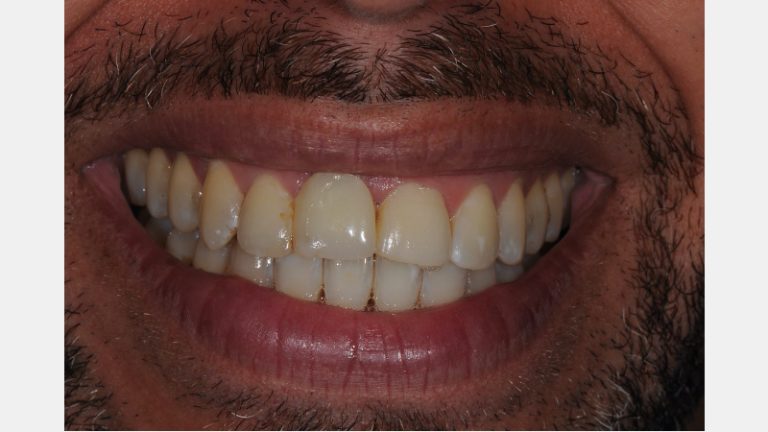

Customized Impression Coping for a Single Tooth Implant in a Maxillary Central Incisor

Follow this visual essay for steps to fabricate a personalized impression coping to optimize the transfer of the peri-implant soft tissue architecture to the laboratory.